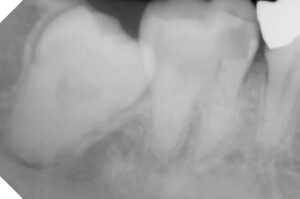

明らかな虫歯の拡大ではないかとレントゲンを撮り

保険にて根の処置をしてレントゲン確認した時に

2017年8月 再来時に左下第二大臼歯のレントゲン

レントゲンを撮影し以前と比較説明してから

レントゲンでは神経の詰め物の状態の違い→

歯根の崩壊度は経時的なもの?→